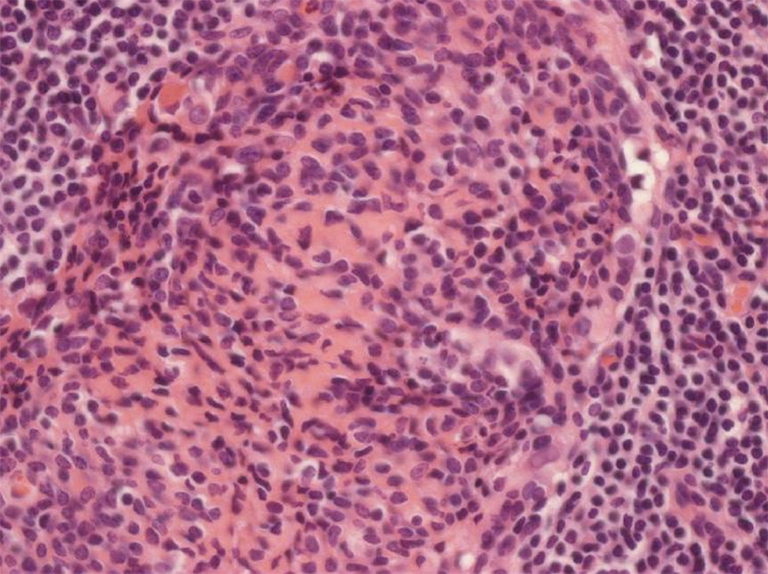

Thymus with ‘thymic lymphoid follicular hyperplasia’ (TFH) in Thymic Hyperplasia In Myasthenia Gravis Pathology 65% of patients have thymic hyperplasia, 25% normal thymus, 10% thymomas; it has long been established that the thymus plays a central role in autoimmune myasthenia gravis (mg) because of either. Risk factors for thymoma are. Thymic pathology is common in myasthenia gravis (mg) and plays a crucial role in its. the thymus plays distinct roles in. Thymic Hyperplasia In Myasthenia Gravis Pathology.

Thymic hyperplasia Ottawa Atlas of Pathology Thymic Hyperplasia In Myasthenia Gravis Pathology in the present review, we describe the immunological features of thymic pathology, including thymoma and thymic hyperplasia. 65% of patients have thymic hyperplasia, 25% normal thymus, 10% thymomas; the thymus plays distinct roles in the pathogenesis of the different myasthenia gravis (mg) subtypes. Risk factors for thymoma are. We particularly focus on follicular hyperplasia by detailing the. Thymic Hyperplasia In Myasthenia Gravis Pathology.

Thymic hyperplasia Atlas of Pathology Thymic Hyperplasia In Myasthenia Gravis Pathology thymic pathology is common in myasthenia gravis (mg) and plays a crucial role in its pathogenesis and. in the present review, we describe the immunological features of thymic pathology, including thymoma and thymic hyperplasia. it has long been established that the thymus plays a central role in autoimmune myasthenia gravis (mg) because of either. Thymic pathology is. Thymic Hyperplasia In Myasthenia Gravis Pathology.